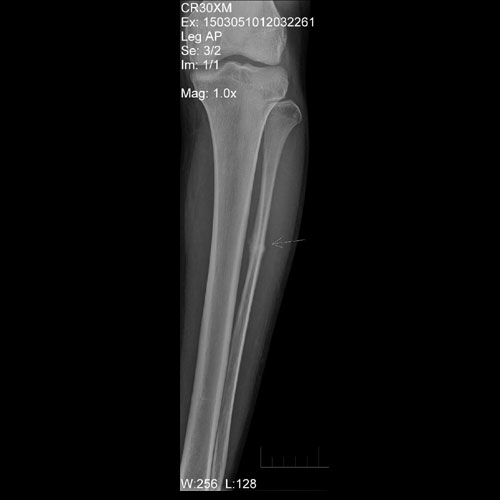

24 year old soldier with pain in mid leg. X Ray of leg shows stress fracture at mid third fibula with callus formation.